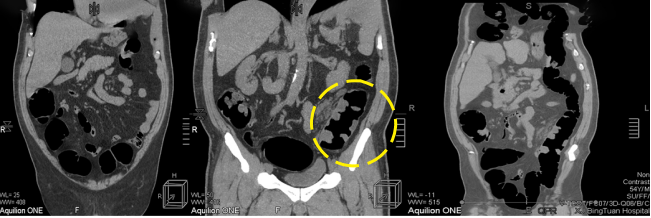

病例三 男,54歲,10小時(shí)前無(wú)明顯誘因突然出現(xiàn)右側(cè)胸背部疼痛,呈脹痛,伴有大汗、頭暈癥狀。

腹盆腔CT腸道充氣成像可見(jiàn)橫結(jié)腸脾曲結(jié)腸癌, 升結(jié)腸及降結(jié)腸多發(fā)息肉

腹腔鏡見(jiàn)腹腔粘連較重, 轉(zhuǎn)開(kāi)腹手術(shù), 取左側(cè)腹直肌切口, 逐層進(jìn)腹, 于橫結(jié)腸脾曲觸 及一腫塊, 遂行左半結(jié)腸切除術(shù)。

640層寬體探測(cè)器CT掃描速度快, 掃描時(shí)間只用了2 . 3 s,克服了胃腸道蠕動(dòng)造成的偽影 和漏層, 使腹部圖像質(zhì)量大大提高。 仿真內(nèi)窺鏡的圖像可觀察到黏膜的皺襞 , 不僅可清晰的 顯示小息肉及病變 , 而且可顯示出胃腸道造影及內(nèi)窺鏡易于遺漏的部位。